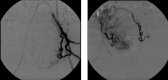

Introduction: Uterine leiomyomas are the most common benign pelvic tumors in women over 35 years and can be symptomatic or asymptomatic. Among the main treatment strategies, there are hormone therapy, hysterectomy, myomectomy, and uterine artery embolization (UAE), a recent and promising treatment for patients who wish to avoid hysterectomy. Ideal candidates for UAE are women with symptomatic uterine leiomyomas that present no desire for pregnancy, premenopausal and heavy menstrual bleeding, or dysmenorrhea caused by intramural fibroids. Case Presentation. A 36-year-old female diagnosed with leiomyomas and an extensive history of failed previous treatments who, in order to preserve her uterus, underwent UAE and had tumor expulsion 15 days after the procedure. The patient remained eight months in amenorrhea and, currently, presents normal hormone levels and irregular periods.